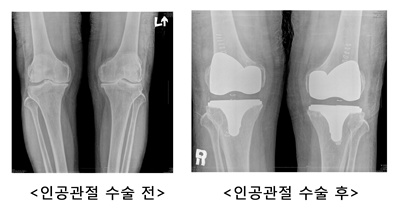

문제는 통증 때문에 야외활동은 커녕, 마트에 장을 보러 가는 사소한 일상에까지 제한을 받게 되면서 심리적으로도 위축될 수 있다는 것이다. 더불어 줄어든 활동량으로 체중은 불어나게 되고 무릎이 받는 하중은 1kg당 3-5배 증가해 퇴행성관절염을 악화시키는 악순환이 반복된다. 이처럼 퇴행성관절염으로 노년 삶의 행복을 위협받고 있는 환자들에게 있어 인공관절수술이 예전의 삶으로 돌아가기 위한 최선의 수단으로 여겨지고 있다.

물론 예전에는 수술에 대한 막연한 불안감과 걱정으로 인공관절수술을 꺼리는 환자들이 많았다. 하지만 최근에는 인공관절의 재질과 수술기법의 발달로 환자의 상태에 따른 맞춤 시술이 가능해지고, 무엇보다 삶의 질을 최우선으로 생각하는 노년층이 증가하면서 인공관절수술을 통해 통증 없는 생활을 되찾는 사람들이 늘어나고 있다.